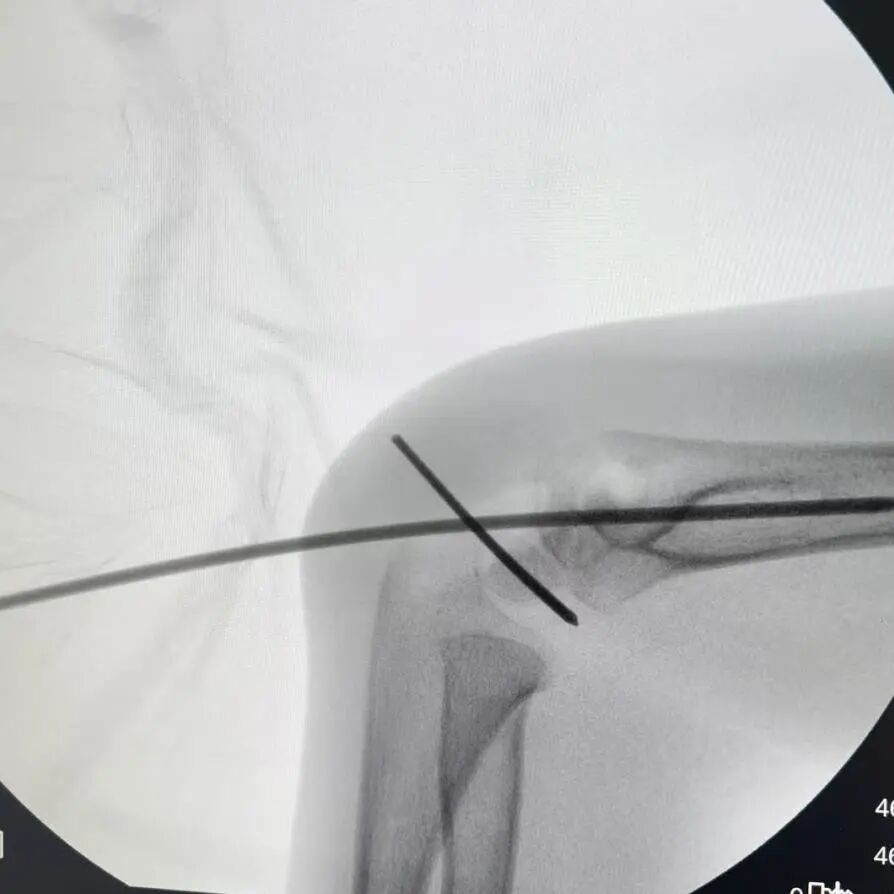

同样“抢时间”的还有小罗和小周的治疗:4岁小罗9月15日深夜入院,10小时后顺利手术;7岁小周同一晚受伤,也在10小时内完成肱骨髁上骨折闭合复位经皮固定术。6岁小郑更是创下“4小时极速手术”纪录——早晨7点40分受伤,8点多入院,11点多手术结束,当天下午就能躺上网课。

“我们的目标是‘24小时内完成急诊手术’,尽量让孩子少耽误一节课。”骨伤科手外·儿骨·烧伤整形组主任陈孝均教授介绍,为了实现这个目标,团队制定了专属流程:孩子入院后,急诊优先开具检查单,放射影像科快速出片;骨科医生同步评估病情,确定手术方案;麻醉科提前做好准备,只要术前检查合格,立刻安排手术——哪怕是深夜或周末,团队也随时待命。